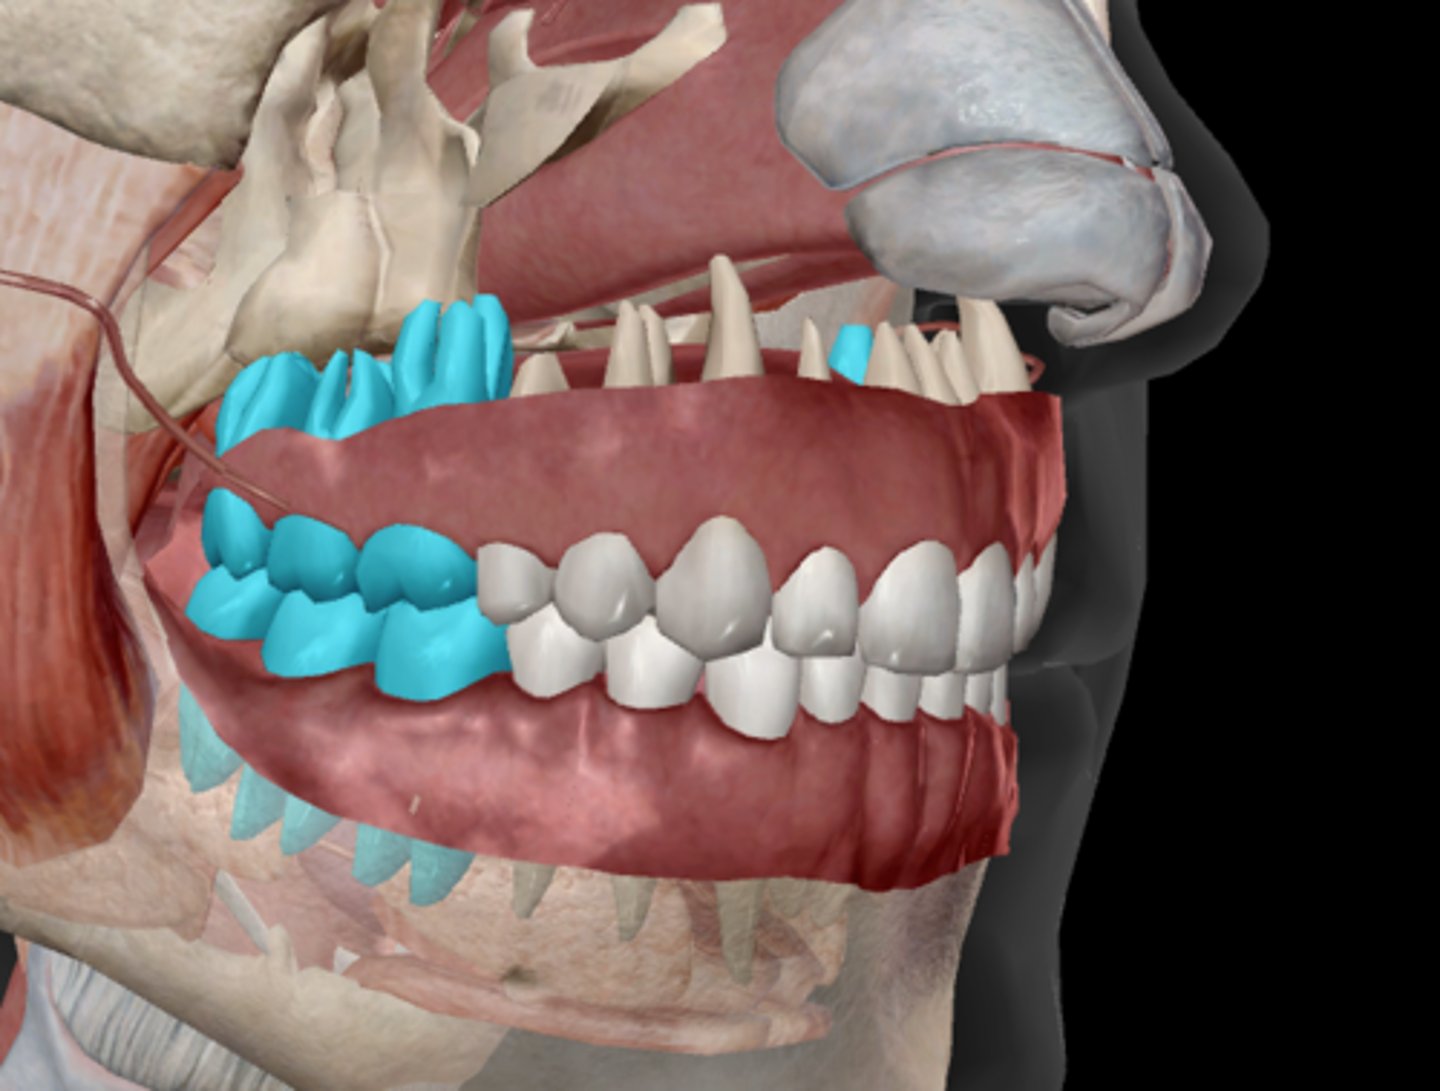

Incisor

Canine (cuspid)

Premolar (bicuspid)

Molars